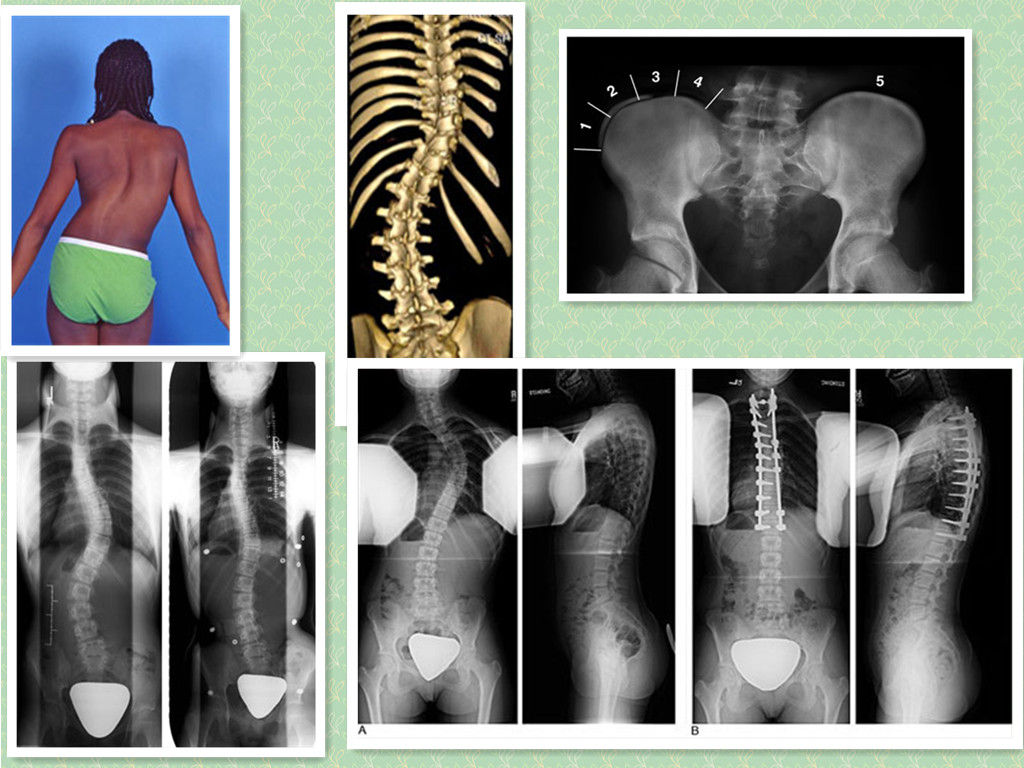

脊柱侧弯类型图

脊柱侧弯类型图,脊柱侧弯图片

哪些脊柱侧弯需要手术治疗

脊柱侧弯图片

脊柱侧弯图片严重图片

脊柱侧弯真人图片

脊柱侧弯手术